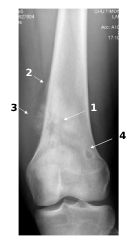

Fig. 120.2 Radiographie de face du tiers inférieur du fémur chez un patient de 12 ans.

Il existe une ostéolyse géographique irrégulière, mal limitée, avec des zones d’ostéocondensation (1). La lésion envahit les tissus mous adjacents (2), avec une réaction périostée plurilamellaire interrompue (un éperon ou triangle de Codman) (3). L’âge, la localisation métaphysaire, le caractère très agressif et l’existence d’une matrice tumorale calcifiée suggèrent un ostéosarcome. Une telle lésion impose une prise en charge oncologique spécialisée, un bilan d’extension locorégional et une biopsie. Pour mémoire, présence d’une lésion bénigne : fibrome non ossifiant condylien interne (4).

Source : CERF, CNEBMN, 2022.